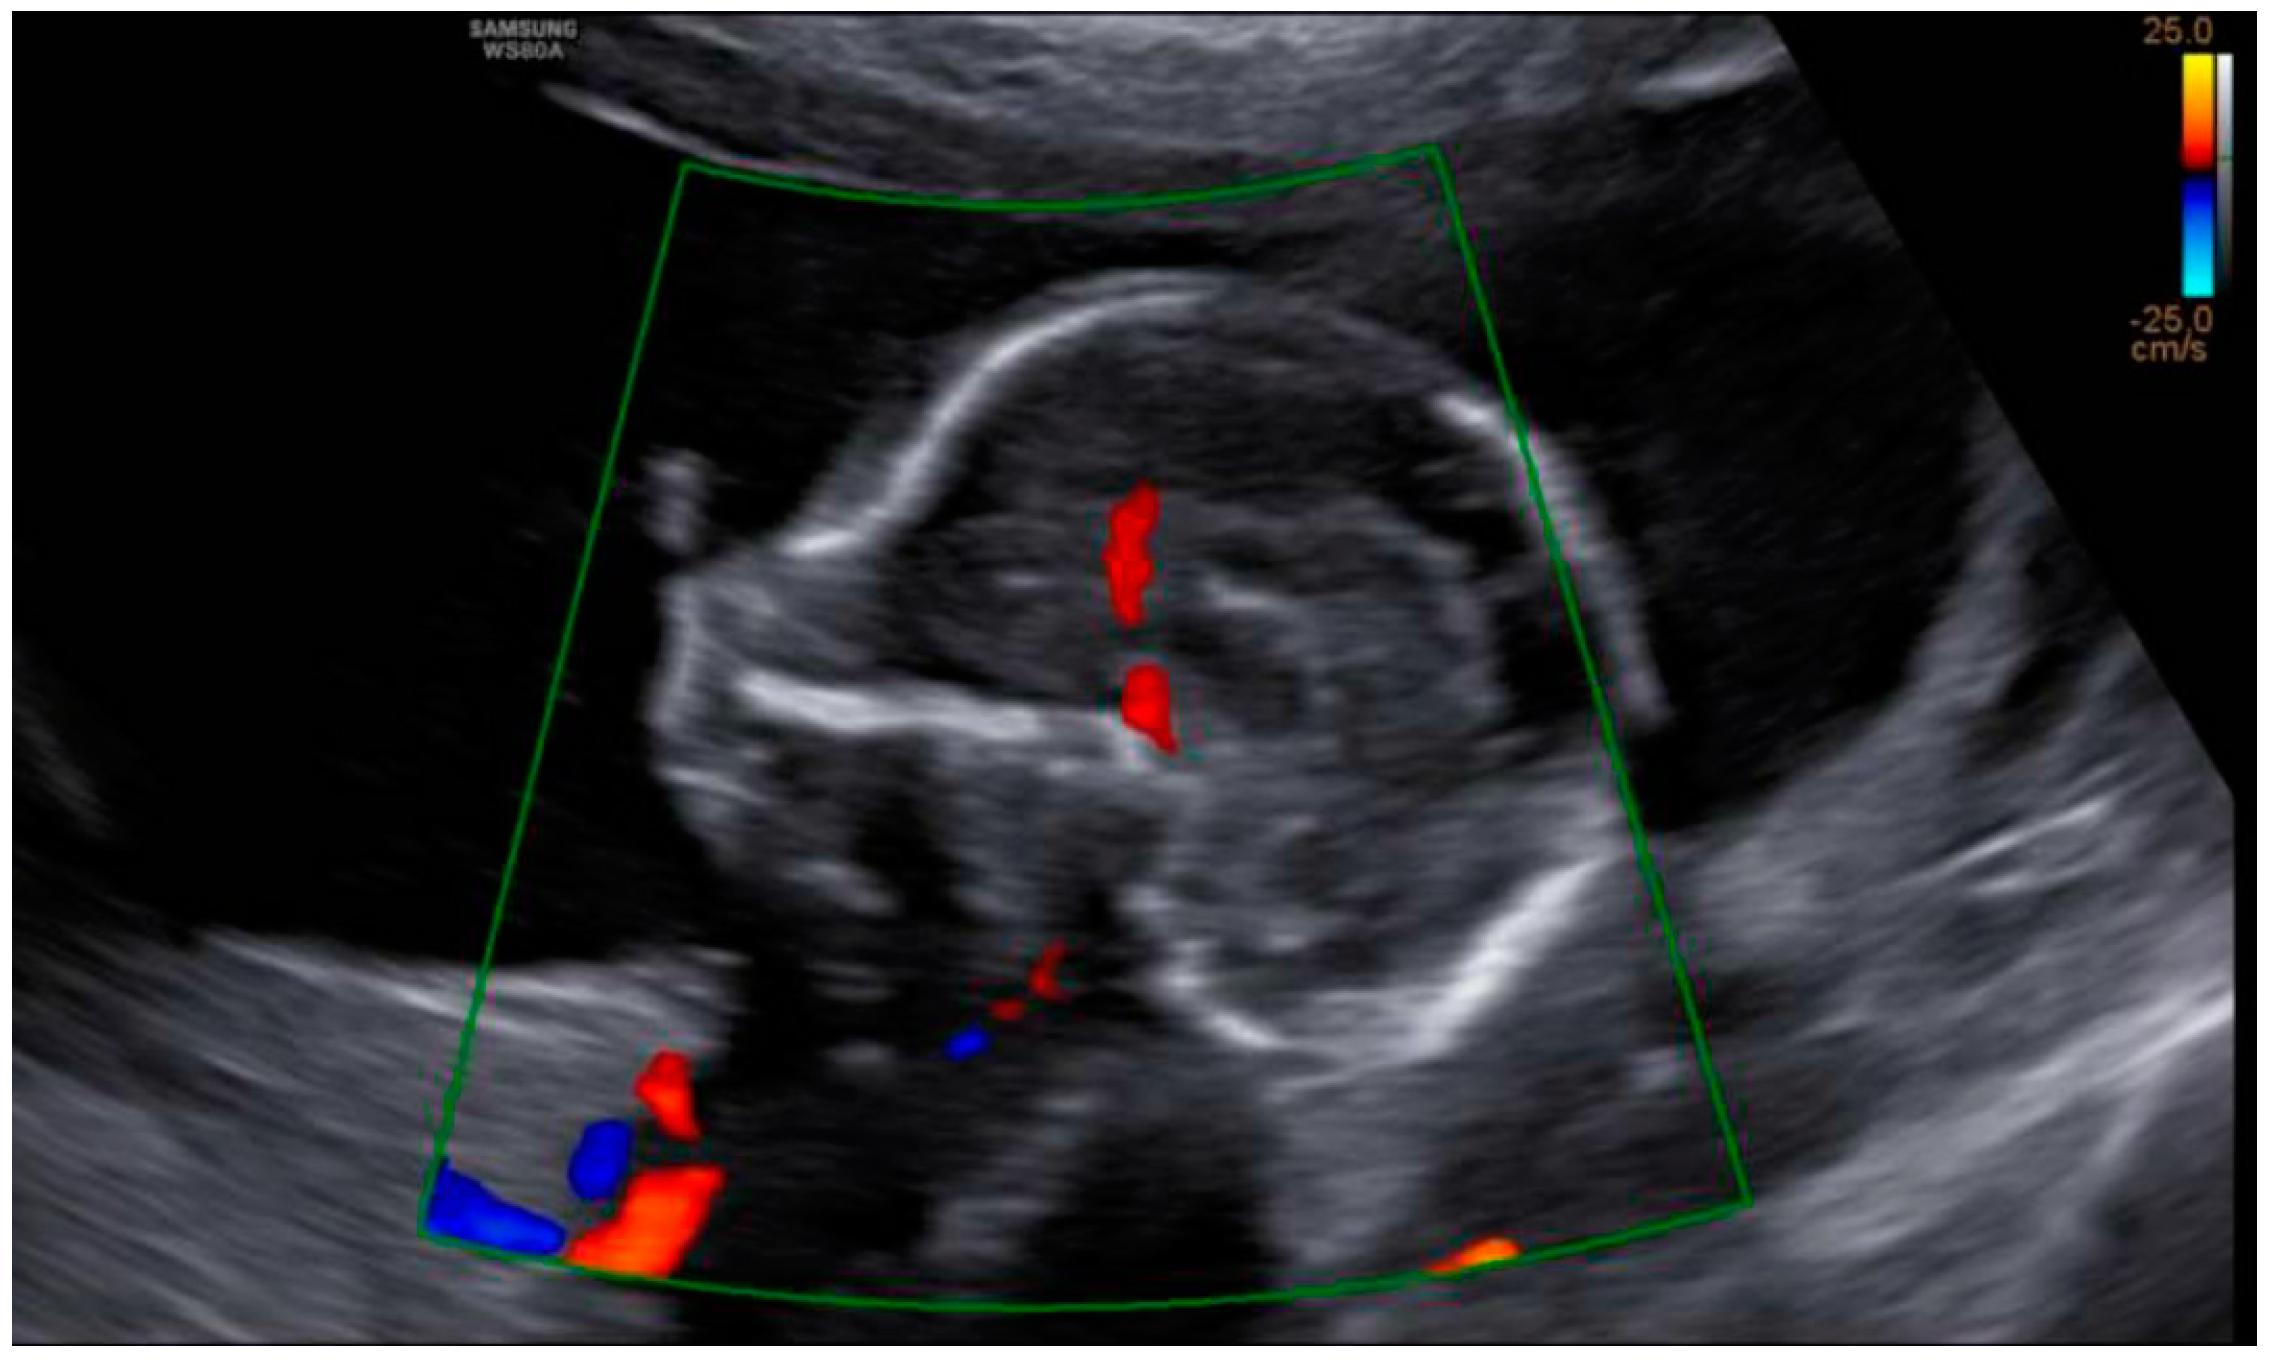

3. Results: Case Presentation